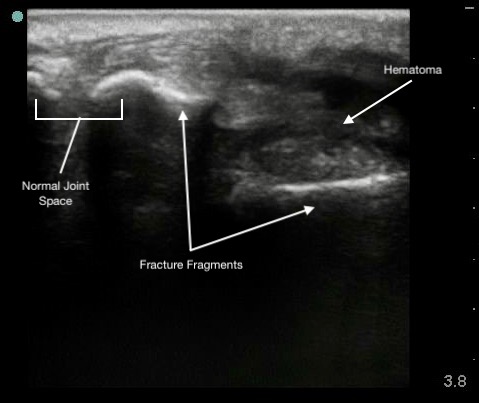

Fractures

Appear as a sharp discontinuity in the bright line of the bony cortex on ultrasound.

Hypoechoic hematoma or effusion may be visible in the surrounding soft tissue.

Ultrasound allows immediate assessment of the presence and extent of a fracture at the area of tenderness.

Capable of detecting displacement as small as 1 mm.

Shoulder Dislocation

Figure 9.

Anterior shoulder dislocation with overlying hematoma